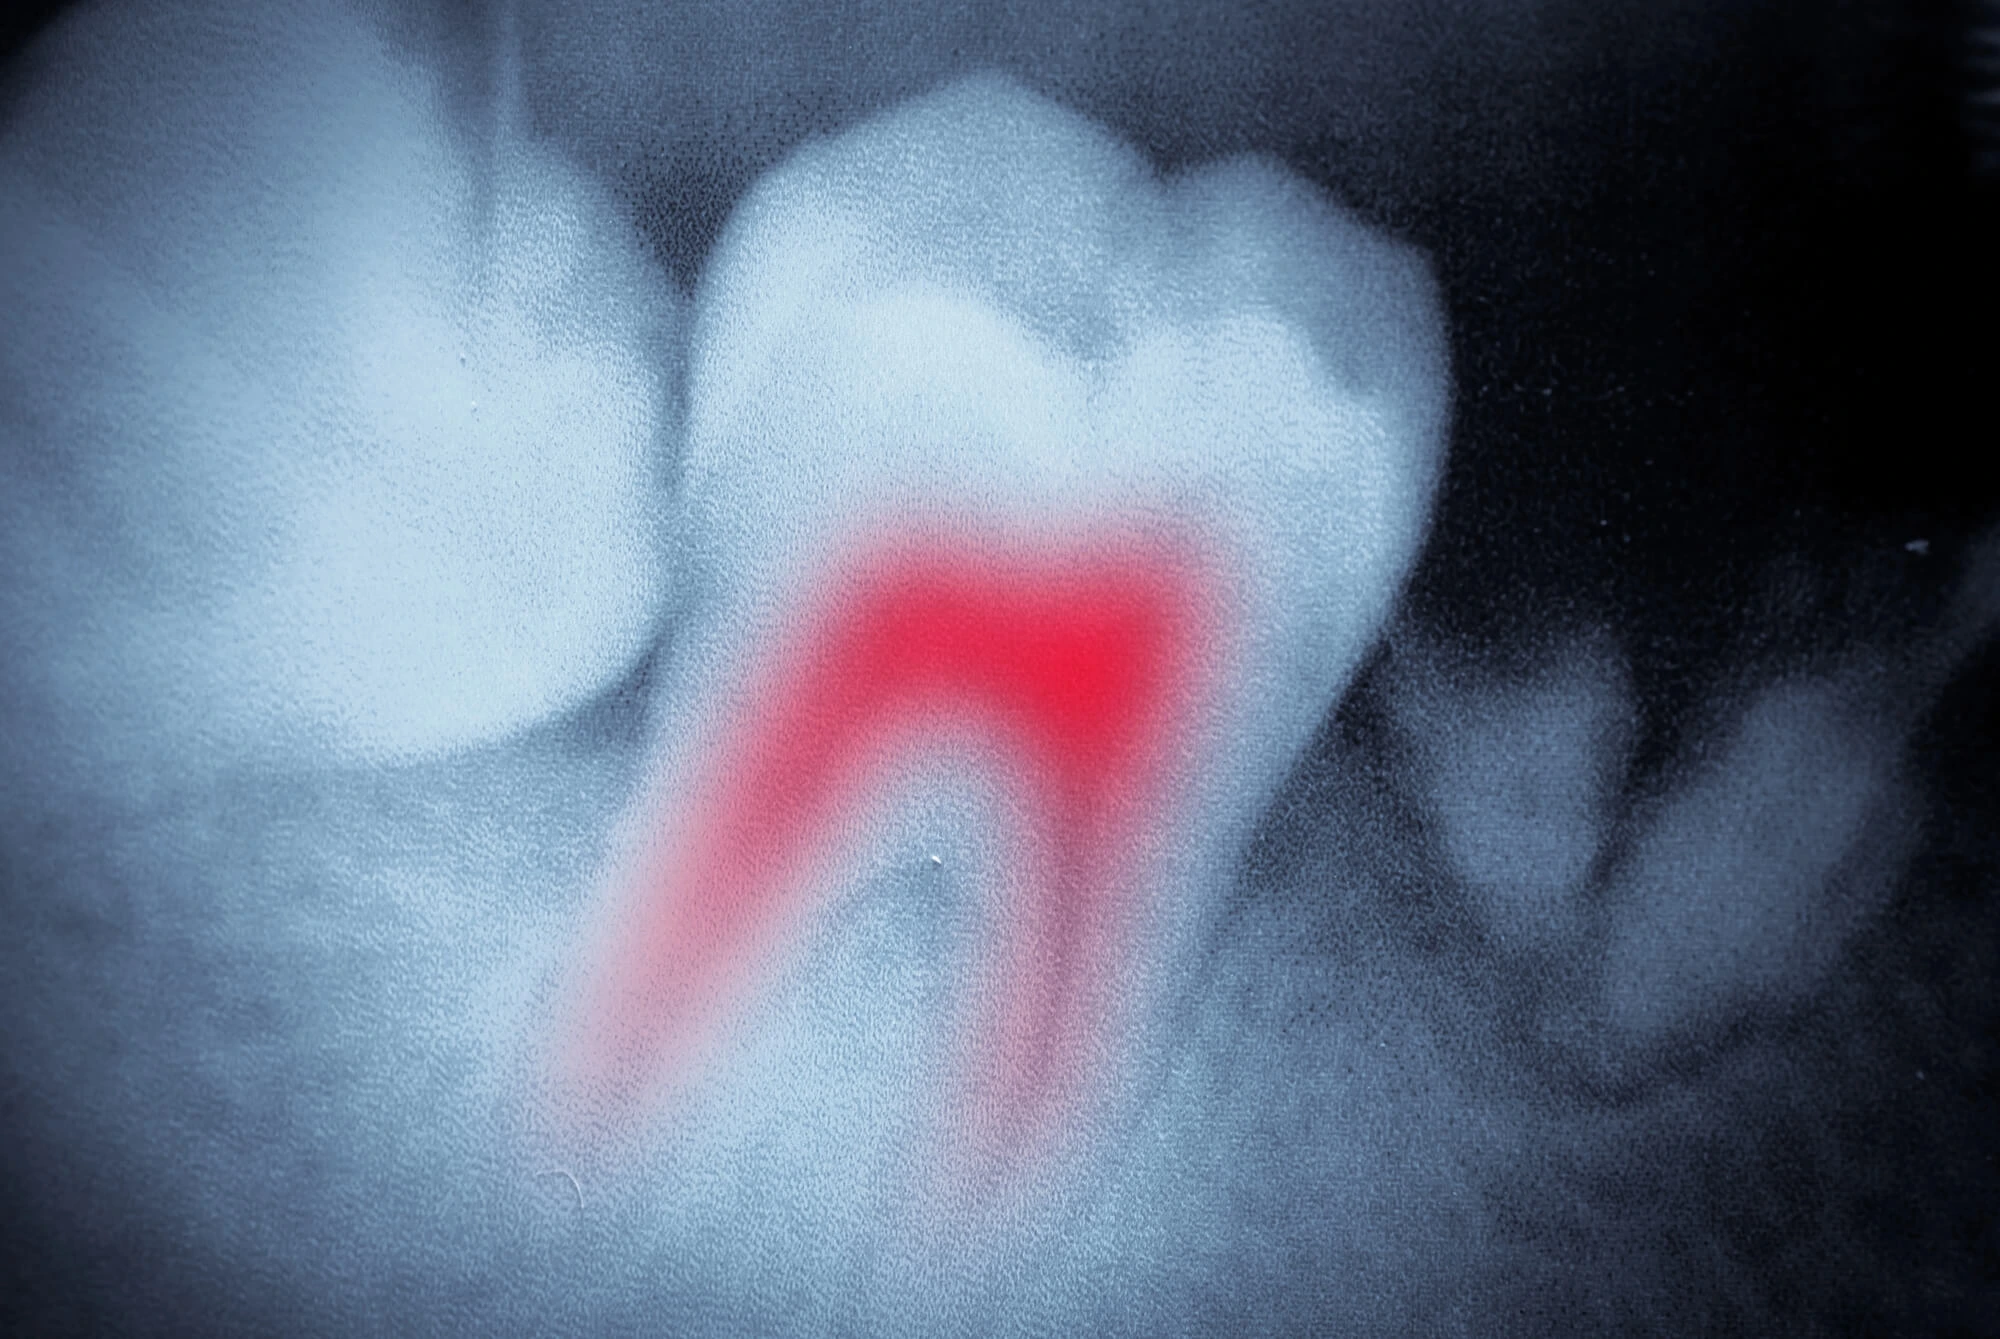

When a cavity reaches deep into the tooth, bacteria can infect the pulp, which houses nerves and blood vessels. Fillings or crowns alone cannot stop the infection once it has spread this far.

A root canal removes the infected pulp while keeping the tooth's outer structure intact. This treatment allows you to avoid extraction and maintain your natural bite.

A root canal clears out the infection, disinfects the inside of the tooth, and seals it to prevent reinfection. The infection can spread to other areas without treatment, creating serious health risks.